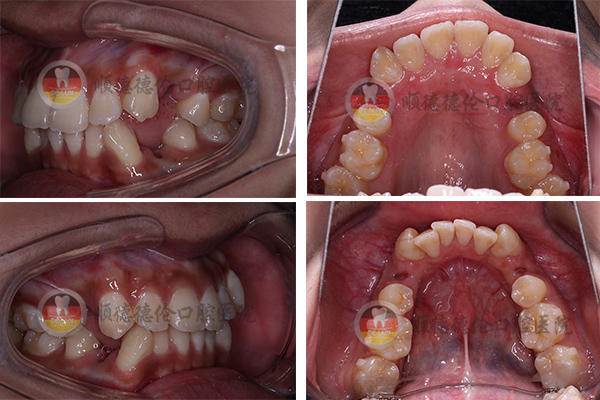

今天我們的【整牙日記系列】主角就是一位有著虎牙的姑娘,她將和我們分享她的整牙日記。

(露齒笑的照片少之又少,好不容易扒拉出一張。我的小虎牙清晰可見)

牙齒狀況:牙齒外突、擁擠、不整齊

我的牙齒前突,我自己覺得很明顯。每想開懷大笑時都要遮遮掩掩,生怕別人因為我的牙齒不好看,反而笑話我,無形中增加了我的心理負擔;另外,因為牙齒不齊,有些地方很難刷干凈。

3、拍口內照